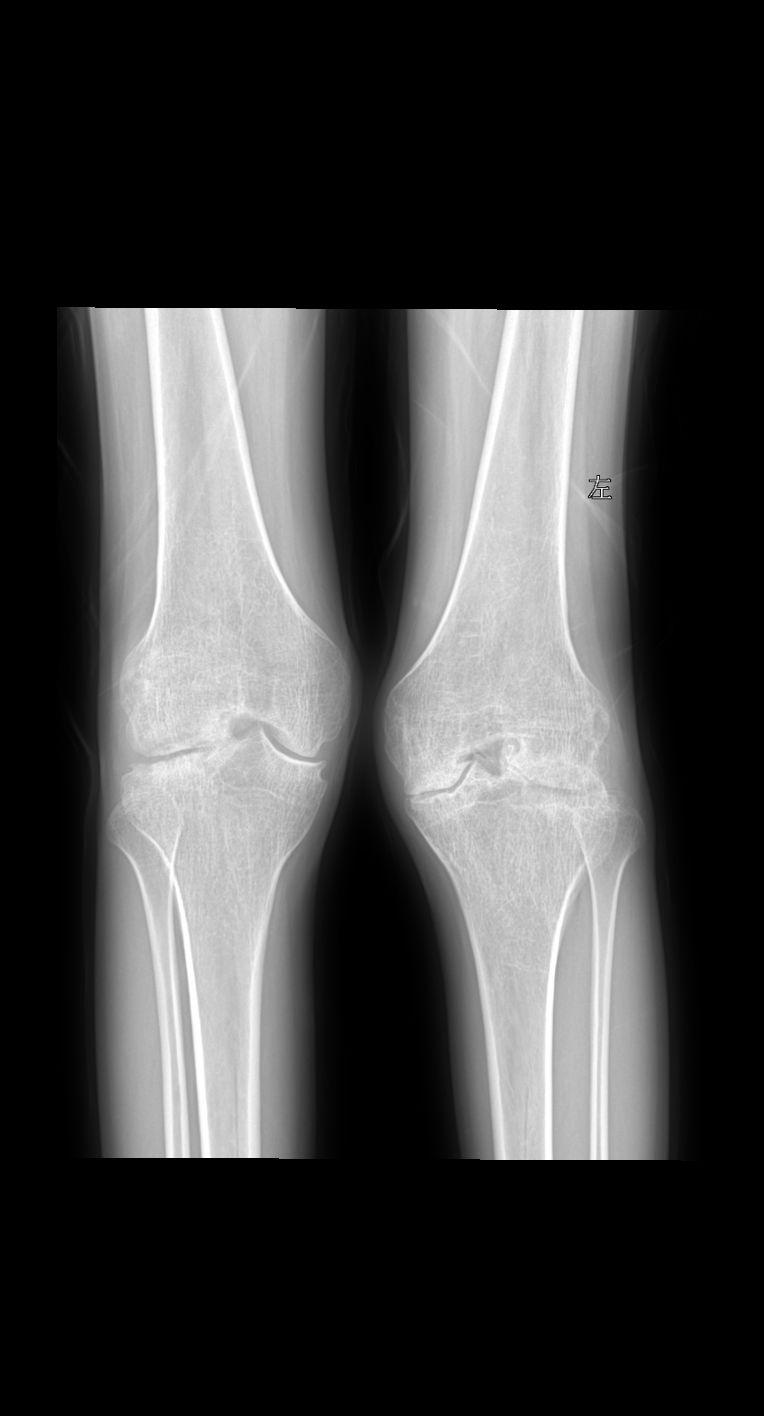

患者女 74岁行走时膝关节疼痛就诊

血友病